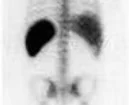

Bone Scans

Bone scans are a sensitive test for evaluating almost any process affecting the skeleton, like bone tumors, fractures, infection, inflammation and many other conditions. The study may be abnormal days or weeks before there are symptoms or changes on plain x-rays. The study is usually completed at one visit, requiring anywhere from one to several hours depending on the reason for the study. SPECT imaging can be performed to give three-dimensional imaging that can be compared directly to images from a CT or MRI. Serial examinations over months or years can document the extent or severity of a disease process over time.